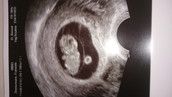

Bei mir ist alles gut bin bei 5+6 und das herzchen hat geschlagen